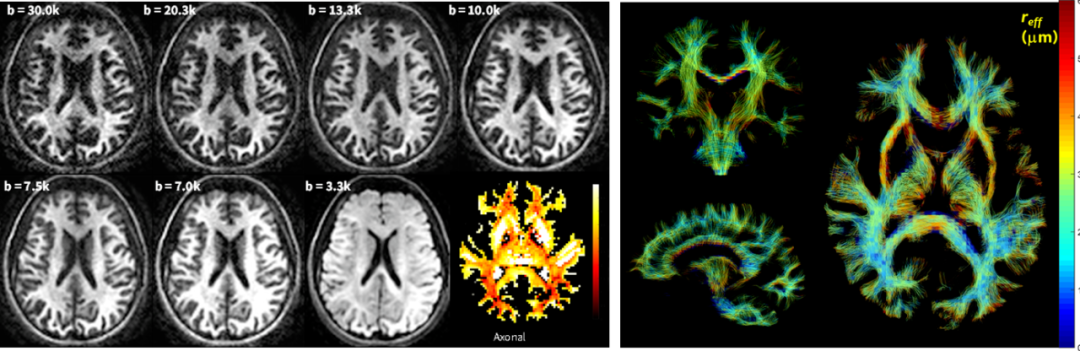

微脑解析:基于SIGNA MAGNUS平台,高梯度场强切换率性能下,使用超高30000B值弥散成像,大幅剔除小轴突测量中不同伪影因素的影响,成功对微脑损伤患者进行了1μm及以下的轴突直径进行解析显示,为微脑的损伤以及机制研究带来全新的临床研究尺度。